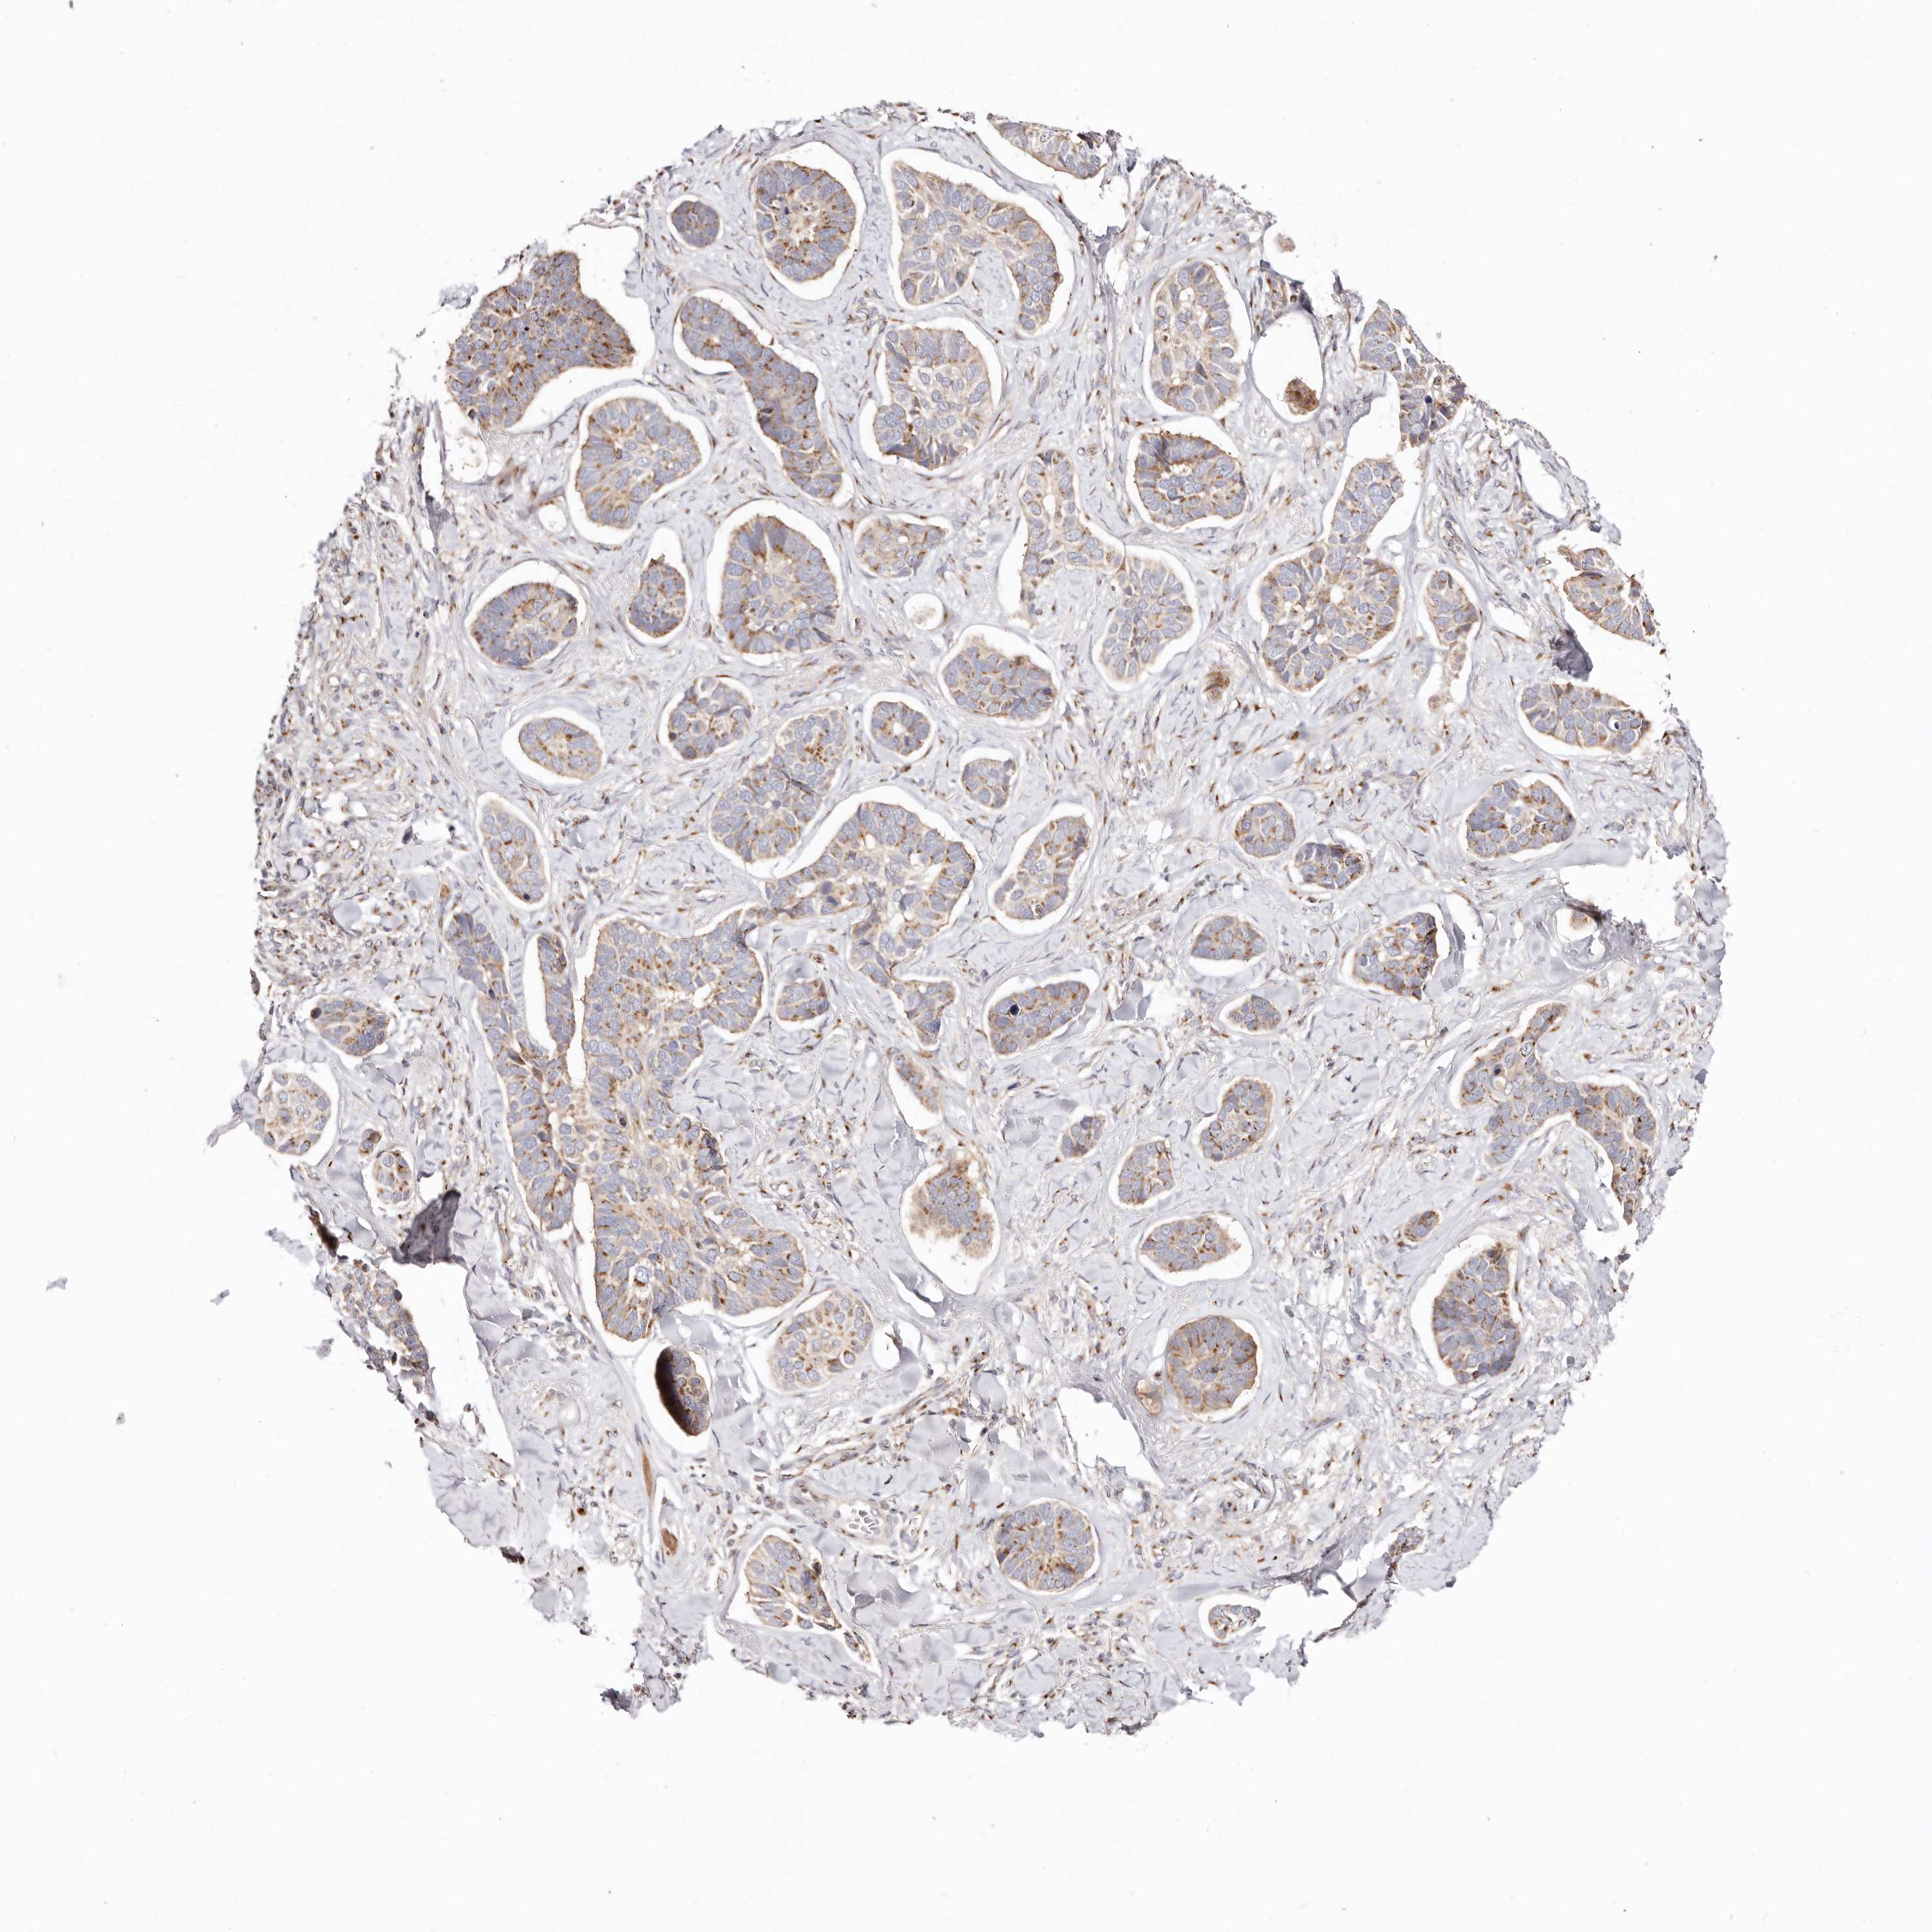

Basal cell and squamous cell cancer

SKIN CANCER - Protein expressioni

A mouse-over function shows sample information and annotation data. Click on an image to view it in a full screen mode. Samples can be filtered based on level of antibody staining by selecting one or several of the following categories: high, medium, low and not detected. The assay and annotation is described here.

Each image is clickable and will lead to virtual microscopy that enables deeper exploration of all samples and also displays staining intensity scores, fraction scores and subcellular localization as well as patient and tissue information for each sample.

Antibody HPA030262

Antibody HPA047825

Antibody CAB005184

Basal cell carcinoma

Squamous cell carcinoma, NOS

Squamous cell carcinoma, metastatic, NOS